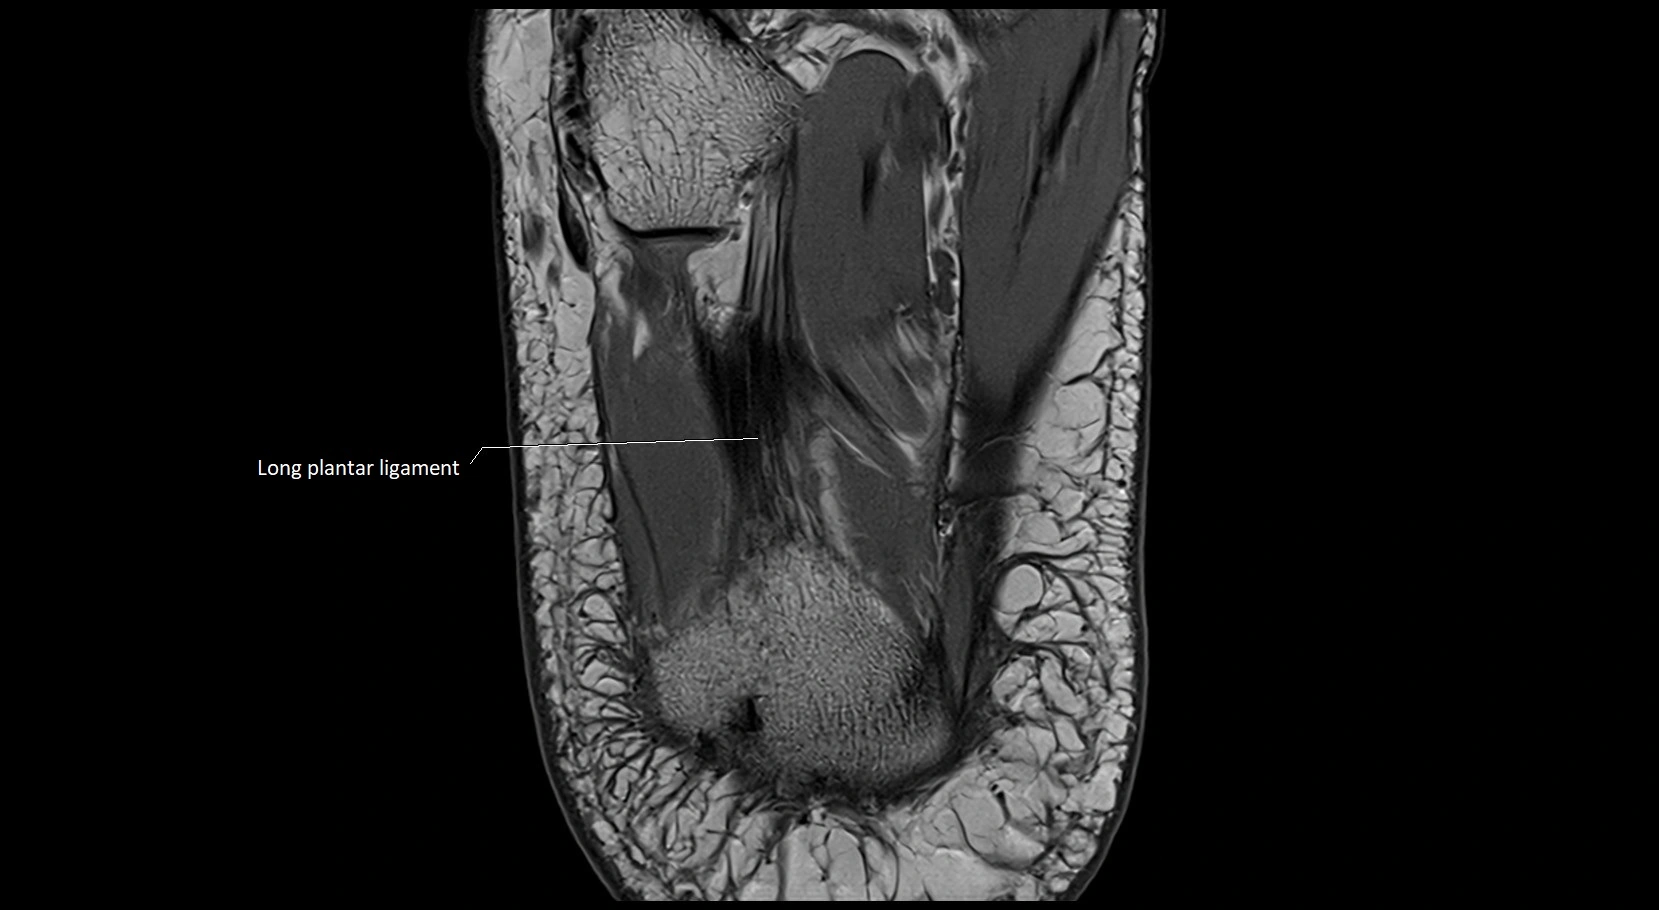

MRI image

image